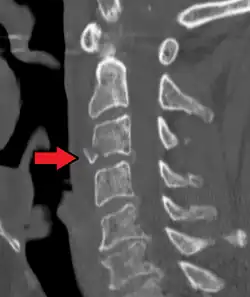

On CT scan or X-ray, a cervical fracture may be directly visualized. In addition, indirect signs of injury by the vertebral column are incongruities of the vertebral lines,[7] and/or increased thickness of the prevertebral space:[8]

-

X-ray of normal congruous vertebral lines -

![CT scan of normal congruous vertebral lines[7]](./_assets_/Vertebral_lines.png)

![CT scan with upper limits of the thickness of the prevertebral space at different levels[8]](./_assets_/CT_of_prevertebral_space.jpg)